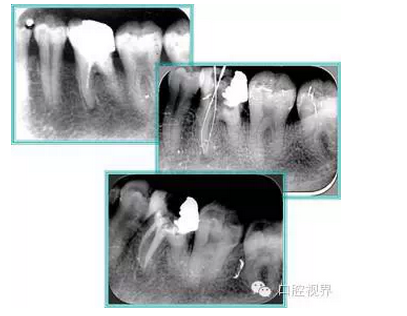

7. 器械折斷

右圖及下圖為器械折斷的 X 線片。箭頭處示折斷器械。

解決方法: ( 1 )取出。 ( 2 )通過。 ( 3 )重新確定工作長度,充填。 ( 4 )根尖手術(shù)。

器械折斷可以不用取出,取出的原因多是患者心理因素。留在里面的器械關(guān)鍵是進行消毒,預(yù)防性使用抗感染藥物,預(yù)防感染。